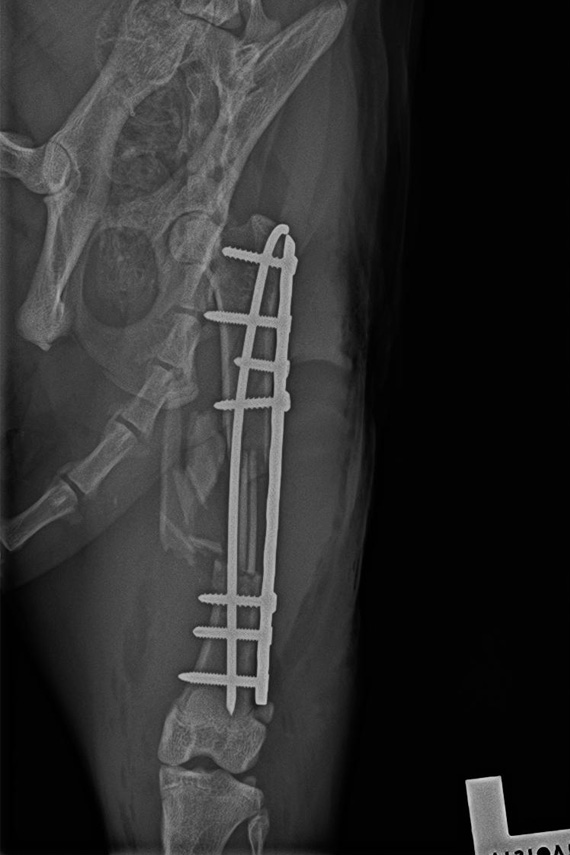

Versorgung Femurfraktur

Versorgung der Femurtrümmerfraktur der Katze aus Abb. 1 mit Platte und IM Nagel (Plate and Rod).

Seitliches Kontrollröntgen nach Versorgung Femurfraktur

Seitliches Kontrollröntgen: eine sehr stabile Versorgung dieser sehr instabilen Fraktur.